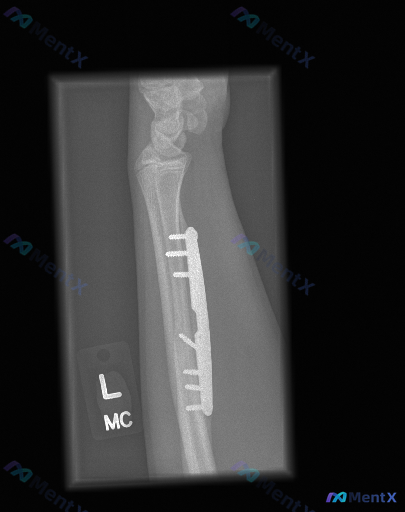

整理到一个左前臂桡骨骨折术后复查的影像相关讨论点,大家看看这种情况会怎么判断: 基本背景 - 左前臂桡骨骨干骨折,已行切开复位内固定术 - 本次复查为左前臂侧位X光片 影像观察到的客观表现 - 桡骨背侧可见金属接骨板及数枚螺钉,位置固定,未见明显松动、断裂或移位 - 骨折断端区域有骨痂生长,骨折线模...